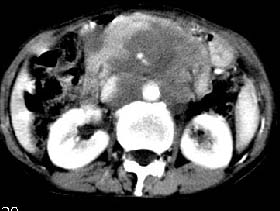

ct:肝胃之间、胰头后、腹主a周围,融合而成团块状影,包绕血管,胰腺前移后缘分界欠清,与肝胃分界清,肿块未见明显强化,肝右叶后段小囊肿。

肝胃之间、胰头后、腹主a周围,融合而成团块状影,包绕血管,胰腺前移后缘分界欠清,与肝胃分界清,肿块未见明显强化,考虑淋巴瘤可能性大

胰腺受压前移,胰管扩张,应为腹膜后占位,病灶密度不均,有低密度坏死区,强化扫描强化不明显腹腔干动脉受侵,考虑腹膜后恶性占位

肝胃之间、肝十二指肠韧带,胰头后、腹主a周围,融合而成团块状影,包绕血管[腹腔干、肠系膜上动脉,腹主动脉],胰腺前移后缘分界欠清,与肝胃分界清,肿块未见明显强化,肝右叶后段小囊肿。

主动脉-胰腺间隙可见巨大分叶状软组织肿块影,包绕腹主动脉、腹腔干及其分支、腔静脉等大血管,增强呈无明显强化,临近脏器明显受压移位,增强示有分界。肝右叶可见局限性低密影,边缘清楚。

影象表现:平扫,首先可见胃壁明显增厚,内外边缘清晰,外缘光滑,内边缘不归整,同时胃腔明显缩小。

再看从肠系膜根部到胰腺后主动脉及上腔静脉周围可见相连的较大的软组织肿块影,形态不规则,呈明显

的大小不等的分叶状,其中密度较均匀但其中可见条状低密度区,肿块边缘比较清晰周围的小肠受压移位

明显且堆积。

增强所见,腹腔动脉,肠系膜上动静脉被肿块包绕,结合平扫的条状低密度区恰好位于血管周围,较大的

肿块强化不明显(遗憾的是没有标上ct值)但胃壁强化的十分明显。